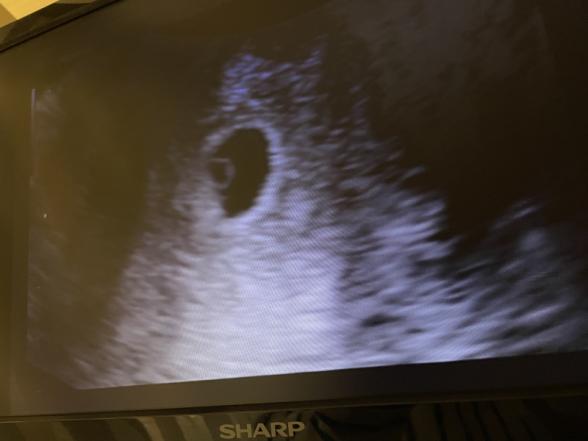

4w4dで2.5mmの胎嚢のようなものを確認。

5w2dで4.0mmの胎嚢のみ確認。

6w0dで8.2mmの胎嚢と卵黄囊確認。

でした。

エコー写真を掲載しておきます。